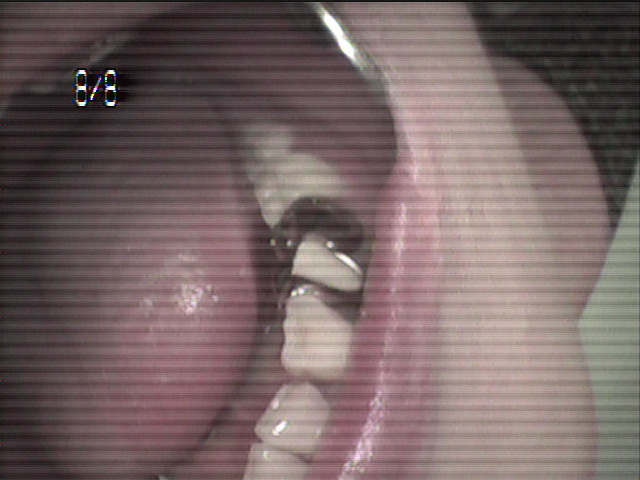

本日、出来上がりました自費の部分入れ歯ー下顎メタルプレートの症例です。

81歳の女性OUさんはとけも若々しいかたで、上下ともに、ぶぶん入れ歯ですが、今回は下顎の左右の奥歯のメタルプレートの入れ歯を新しく作りました。

自費によるメタルプレート義歯で、薄く丈夫な義歯として、とても舌感の良好な状態にすることができ、さらに自由な義歯の設計ができるため、残っているはにかける針金は白金加金で作成し、残存歯にやさしい設計となっており、舌に触れるバー部分はコバルトクロム合金で、丈夫に薄く作ってあります。

(参考代金;30万円)